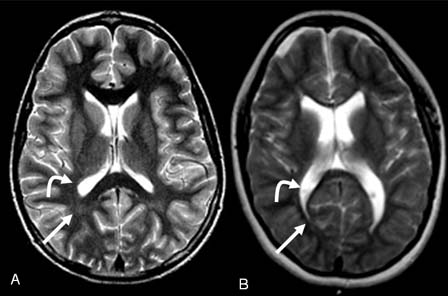

პერივენტრიკულური ლეიკომალაცია. სურათი A წარმოადგენს 14 წლის ჯანსაღ გოგონას: მოღუნული ისარი მიუთითებს ნორმალურ მარცხენა პარკუჭზე, სწორი ისარი კი დაუზიანებელ თეთრ ნივთიერებაზე. სურათი B წარმოადგენს ცერებრული დამბლის მქონე 14 წლის გოგონას: მოღუნული ისარი მიუთითებს გადიდებულ პარკუჭზე, სწორი ისარი კი - თეთრი ნივთიერების შემცირებულ მოცულობაზე, პერივენტრიკულური ლეიკომალაციის გამო

ლოს ანგელესში David Geffen-ის სახელობის სამედიცინო სკოლის რადიოლოგიის დამხმარე პროფესორის, Noriko Solomon-ის საკუთრება